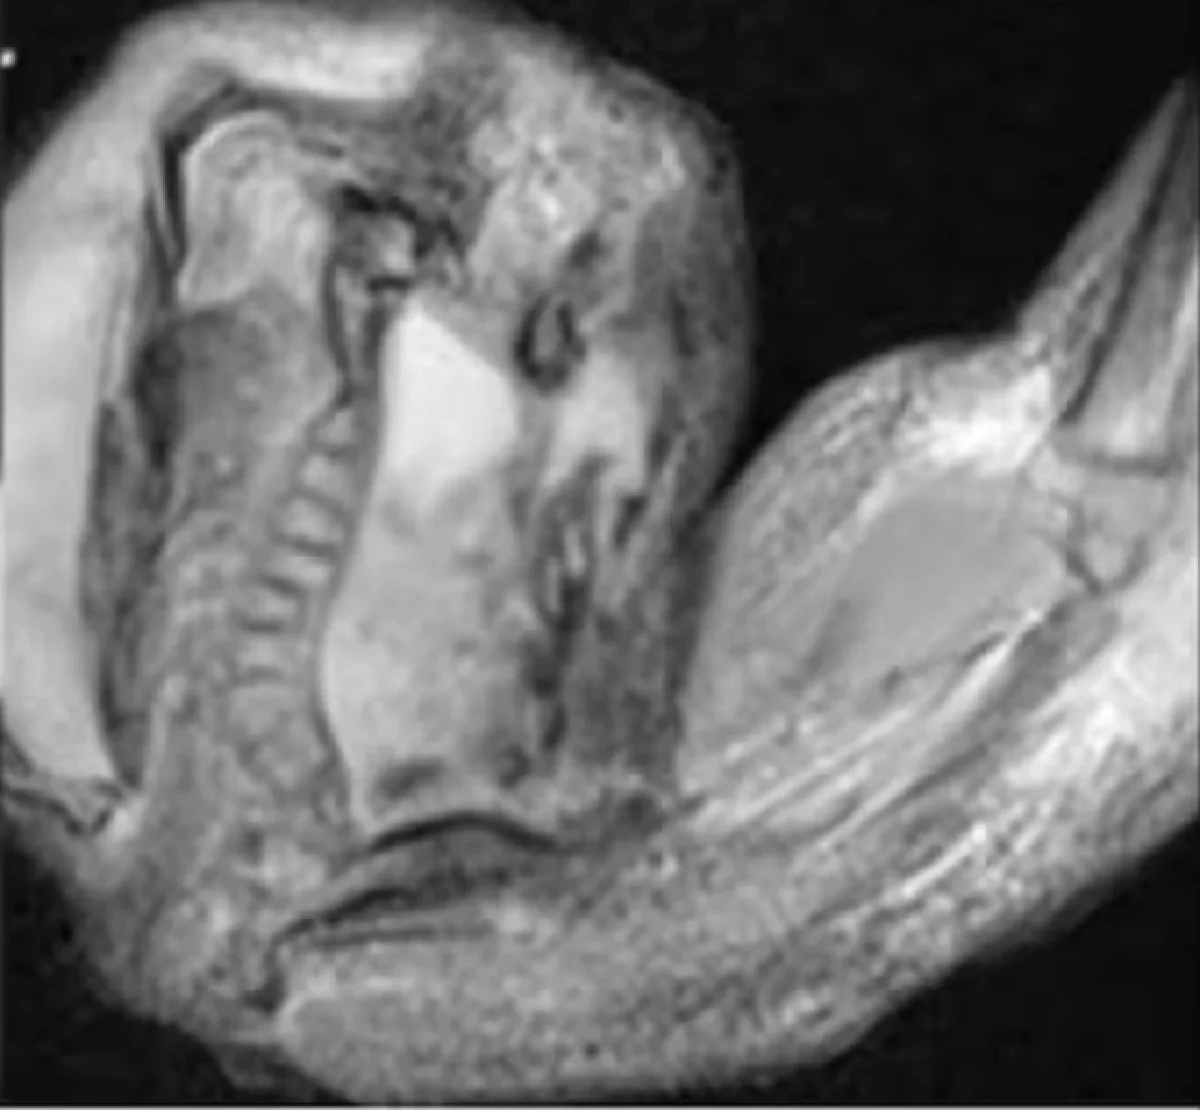

अशा स्थितीत मुलीचे पालक तिला रुग्णालयात घेऊन गेले जेथे तिचे सीटी स्कॅन करण्यात आले. तपासणीनंतर मुलीच्या मेंदूमध्ये भ्रूण  असल्याचे डॉक्टरांना आढळले. डॉक्टरांनी सांगितले की, हा न जन्मलेला भ्रूण  मुलाच्या मेंदूमध्ये 4 इंचापर्यंत वाढला होता. आणि त्याची कंबर, हाडे आणि बोटांची नखेही विकसित होत होती. डॉक्टरांनी सांगितले की, मूल आईच्या पोटात असल्यापासूनच या न जन्मलेल्या भ्रूणचा विकास मुलाच्या मेंदूमध्ये होत होता. मुलीच्या मेंदूतून काढलेल्या या गर्भाच्या जीनोम सिक्वेन्सिंगमध्ये हा गर्भ या मुलीचा जुळा असल्याचे समोर आले. वैद्यकीय शास्त्रात या अवस्थेला भ्रूणातील गर्भ म्हणतात. या स्थितीत आईच्या पोटात वाढणाऱ्या दोन भ्रूणांपैकी एक भ्रूण दुसऱ्या भ्रूणाच्या आत विकसित होऊ लागतो. जेव्हा दोन भ्रूण व्यवस्थित वेगळे होत नाहीत तेव्हा असे होते.

आतापर्यंत, वैद्यकीय इतिहासात गर्भ-इन-गर्भाची सुमारे 200 प्रकरणे नोंदवली गेली आहेत. यापैकी, मेंदूच्या आत भ्रूणच्या विकासाची केवळ 18 प्रकरणे नोंदवली गेली आहेत. बर्‍याच प्रकरणांमध्ये, पोट, आतडे, तोंड आणि अंडकोषात भ्रूण  देखील आढळला आहे.  मुलीला हायड्रोसेफलस नावाची समस्या असल्याचेही डॉक्टरांनी सांगितले. ही अशी स्थिती आहे ज्यामध्ये मेंदूमध्ये द्रव जमा होऊ लागतो. जास्त पाणी साचल्यामुळे त्याचा मेंदूवर परिणाम होतो आणि त्याचे नुकसान होऊ शकते. सहसा लहान मुले आणि वृद्धांना या समस्येला सामोरे जावे लागते.